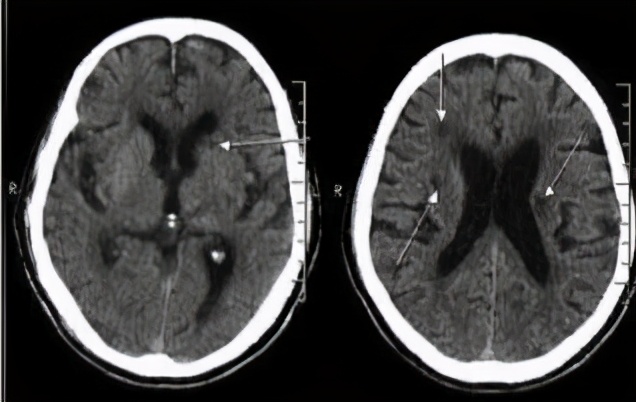

在脑梗死中有一种病灶小(2~15mm),症状不明显的梗死,称为腔隙性脑梗死,多是体检偶然做CT或磁共振检查发现的,也称为静止性梗死,这种脑梗死在60岁以上的人较为常见,尤其是患有高血压的人。虽然腔隙性脑梗死早期症状不明显,但是随着病灶的增多和年龄的增长,患者会出现记忆下降或认知功能障碍,甚至平衡障碍。据美国心脏协会(American Heart Association)估计,超过1300万美国人有过一次或多次这种静止性梗死。

多发性脑梗死

多发性脑梗死痴呆是因为大脑的多处小血管堵塞,导致脑细胞失去氧气和葡萄糖供给,出现痴呆症状。如果在发生脑梗死的过程中有足够多的神经细胞受损或死亡,记忆就无法恢复了。